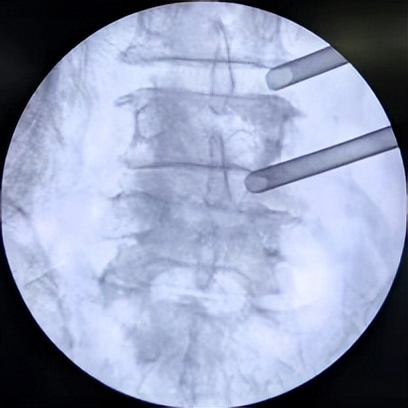

腰3/4、腰4/5两个节段椎管狭窄

66岁男性患者,腰3/4、腰4/5两个节段椎管狭窄,左下肢放射性疼痛、麻木2个月余,间歇性跛行,保守治疗无效。其爱人9年前患腰椎间盘突出症,副主任医师石立刚利用微创椎间孔镜治疗后,至今效果满意。此次慕名前来。

微创椎间孔镜术中